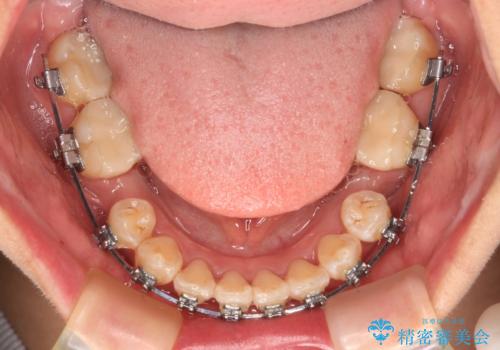

- 矯正装置

- メタルブラケット

奥歯の咬み合わせ改善にはどうしても長期間を要します。

3年強とお伝えしておりましたが、予想通り3年3ヶ月で治療を終えることができました。